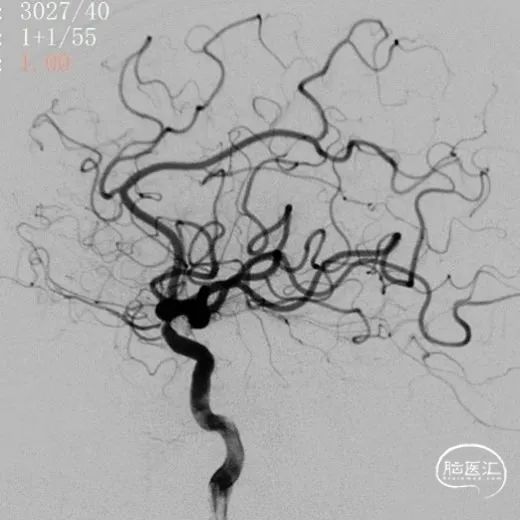

术前影像

术前影像

术前影像